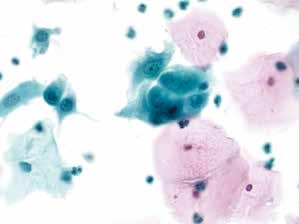

图7-5 满意样本(中倍、液基、巴氏染色)

正常子宫颈管腺细胞,蜂窝状排列,足够数量的鳞状上皮细胞,炎细胞背景。